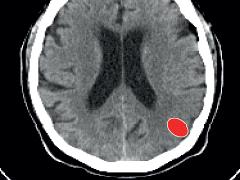

Patiënten met een beroerte, een herseninfarct of een hersenbloeding hebben een betere kans op herstel als zij snel na het begin van de klachten behandeld worden. De eerste 4,5 uur na de beroerte zijn hierbij van cruciaal belang, maar binnen deze 4,5 uur telt eigenlijk iedere seconde. Om de ‘door to needle time’ – de tijd tussen de aankomst bij de Spoedeisende Hulp en het starten van de behandeling – te verkorten, werken medewerkers van het Academisch Medisch Centrum (AMC) in Amsterdam nu nauw samen op de Acute HersenHulp. Dit is een ruimte op de Spoedeisende Hulp (SEH) die speciaal is ingericht voor de behandeling van patiënten met een beroerte. De samenwerking tussen ambulancediensten uit de regio, de afdelingen Neurologie, SEH en de Radiologie van het AMC, vastgelegd in een multidisciplinair behandelprotocol, heeft de doorlooptijd voor de trombolysepatiënten verkort. Vóór de implementatie van de Acute HersenHulp was de ‘door to needle’ tijd gemiddeld nog meer dan een uur. Inmiddels wordt 85% van de patiënten binnen een half uur getrombolyseerd en zijn zelfs doorlooptijden van vijftien tot twintig minuten mogelijk. Hiermee is de kans op een goed herstel na de beroerte aanzienlijk toegenomen.